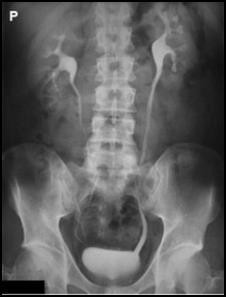

Na rycinie rentgenogramu w projekcji AP symbolem X oznaczono

A. dołek głowy kości udowej.

B. głowę kości udowej.

C. brzeg panewki.

D. szyjkę kości udowej.